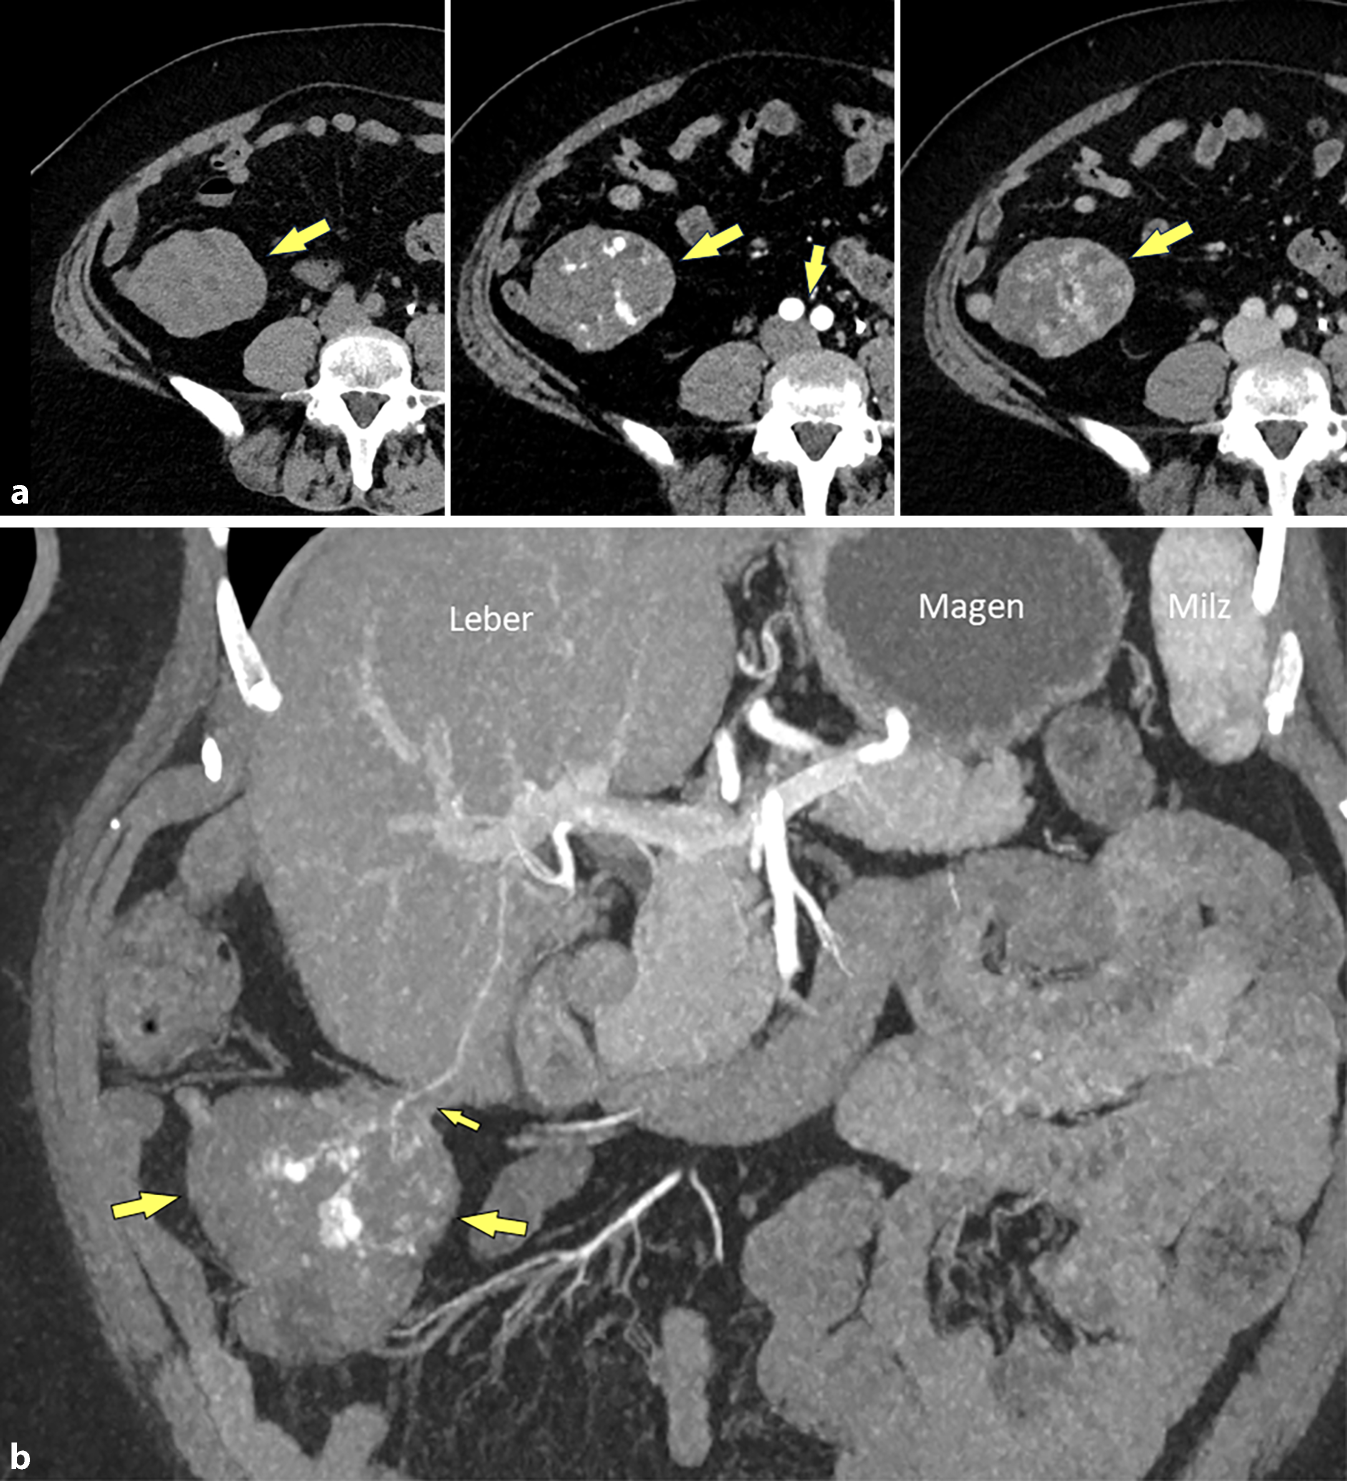

Abb. 3

Kontrastmittel-verstärkte MDCT. a Die dynamische CT (nativ, arterielle Phase, portal-venöse Phase) zeigt ein Hämangiom-typisches fleckiges Kontrastmittel-Enhancement (große Pfeile), ähnlich dem Gefäß-Enhancement auf Höhe der Aortenbifurkation (kleine Pfeile). b Wegweisend für den Ursprung der Raumforderung aus der Leber ist die Darstellung des Gefäßstiels in der coronalen-3D-Rekonstruktion, mit arterieller Gefäßversorgung des Tumors (große Pfeile) aus der Leber (kleiner Pfeil)